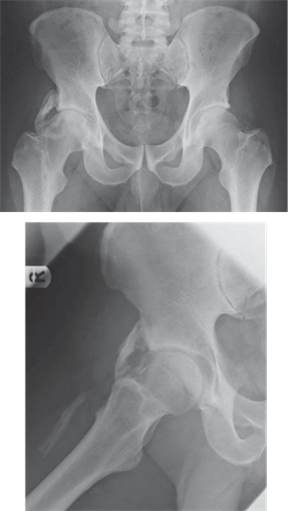

Illustration 1 for Ace FRCS Orthopaedics: Oxford University Press Adult Pathology Viva

Clinical Radiograph / Orthopedic Image

Reproduced from Murray Longmore, Ian Wilkinson, Edward Davidson, Alexander Foulkes, and Ahmad Mafi , Oxford Handbook of Clinical Medicine, fi gure 2, p. 205, 2010, with permission from Oxford University Press.

This is a clinical photograph of a grossly deformed foot and ankle.

Charcot arthropathy is a severe destructive arthropathy which can occur in any patient with a sensory disturbance. Over 90 % of cases in the UK are related to diabetic neuropathy. (It occurs in 1 % of diabetics who have had the disease for 12 years.) The other causes can be thought of along the course of the sensory neurological system from peripheral to central:

z Alcoholic peripheral neuropathy z Post-traumatic sensory deficits z Tertiary syphilis zSpina bifida z Hereditary motor and sensory neuropathy z Congenital insensitivity to pain

The pathophysiology is not fully understood, but is generally thought to be due to a combination of both neurotraumatic and neurovascular factors. It is probably initiated by trauma; however, often no injury can be recollected by the patient. There is rapid destruction of the joint surface and demineralization, which appears to be a due to osteoclast overactivity, bone vascular shunting, and bone breakdown. This leads to loss of normal foot architecture. This phase is often said to be painless, but there is usually some pain (often less than may be expected). Healing begins and there is usually bony union with joint incongruity and foot deformity.

Eichenholz has staged this process:

z Collapse: the foot becomes painful, swollen (oedematous), and warm (erythematous). X-rays may show a fracture/fractures or dislocation. This stage can be difficult to differentiate from an acute infection. Over the following weeks the oedema and erythema settle, although the foot can continue to change shape (unless protected) as the bone continues to fragment. As a general rule, if the skin is intact think Charcot, if the skin is broken it is most likely infection, the history will often lead you

z Coalescence: the foot continues to settle and starts to stiffen up and the deformities become fixed.

X-rays show coalescence of small fracture fragments and adsorption of fine bone debris z Consolidation: over many months the oedema and erythema completely settle. X-rays show consolidation and remodelling of fracture fragments. (As a rough guide: forefoot 6 months, midfoot 12 months, hindfoot 18 months)